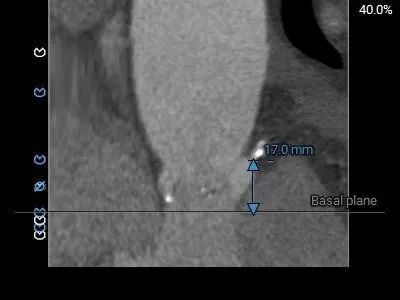

主动脉根部测量:

Type1型二叶瓣,L-R纤维样融合,LVOT偏敞口型,水平夹角72°,严重横位心

•Type1型二叶瓣,L-R纤维样融合,轻度钙化,钙化块主要沿无冠窦瓣叶分布;LVOT偏敞口型;

•-主动脉瓣水平夹角约72°严重横位心,主动脉弓宽度角度可,弓顶部散在钙化分布;